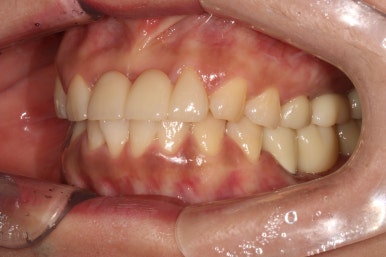

우측 측면 사진입니다.

우히려 좌측에 비해 더 예쁘게 마무리된 것 같아요~

기존에 큰 아말감 치료를 받으셨고, 이차 충치가 심해 검게 보이던 오른쪽 아래 큰 어금니는 이제 하얀 지르코니아 크라운으로 예쁜 모습을 되찾았습니다.

오른쪽 위 어금니들도 뿌리만 남아있던 잔존치근들이 모두 제거되고, 앞니와 같은 하얀색의 치아들로 완전히 대체된 모습을 보실 수 있습니다.